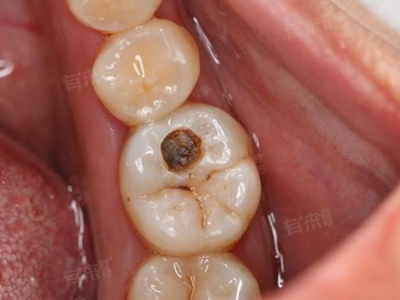

发现牙中间有洞时,及时到口腔科就诊。医生通过口腔视诊观察牙洞深度、颜色及周围组织状态,结合X线片判断龋坏是否累及牙髓,明确牙齿损伤程度,为后续治疗提供依据。

若龋坏仅局限于牙釉质或牙本质浅层,可进行填充治疗。医生清除腐坏牙体组织,消毒窝洞后,选用合适的填充材料填充牙洞,恢复牙齿形态与咀嚼功能,阻止龋坏进一步发展。